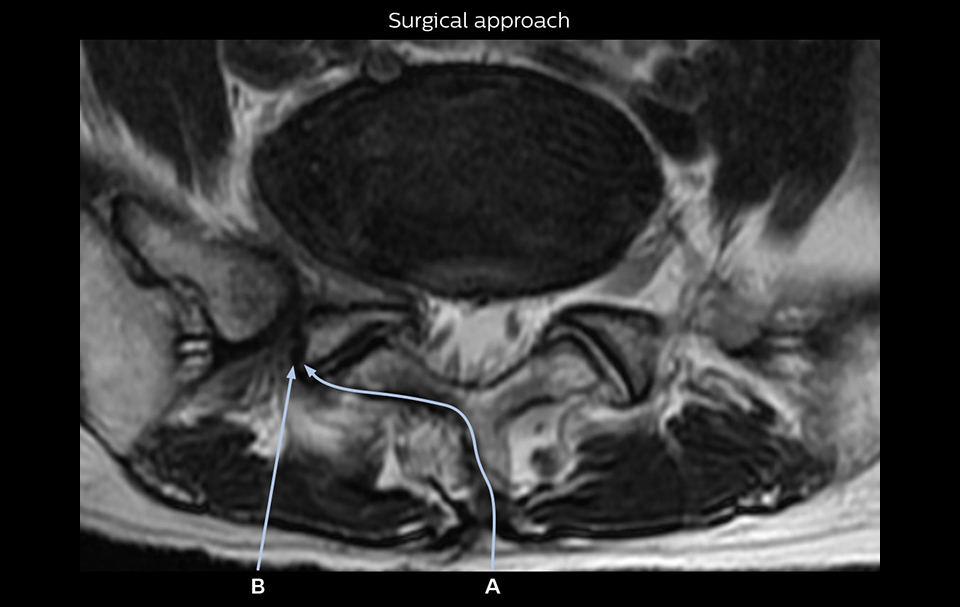

“Recently, the two surgical methods extreme and oblique lateral interbody fusion (XLIF and OLIF) have become mainstream for minimally invasive treatment of lumbar spinal canal stenosis and intervertebral foramen stenosis. With these surgical techniques, the spine is approached from the flank, and prior knowledge of the exact anatomy of the lumbosacral plexus would be extremely helpful. To that end, high slice resolution (less than 1 mm acquisition) that enables sharper sagittal MPR images will be needed.”

The addition of the nerve-selective NerveVIEW sequence to its spine MRI protocol has given NFMC competitive advantages, according to Tanji. “Since we started including NerveVIEW routinely, the demand for lumbar spine MRI examinations has increased, especially for pre-surgical planning purposes and for patients with chronic lower extremity symptoms,” he says. “Moreover, because no other hospitals in our region are doing nerve plexus imaging yet, we often receive referrals for MR neurography studies from other hospitals even if they have an MRI scanner. Some requests come from as far as 100 km away. NerveVIEW definitely provides us a competitive advantage.” “Based on our experience, we can certainly recommend NerveVIEW to other centers,” Dr. Yabuki adds. “The sequence opens up many possibilities to facilitate the diagnosis of lower extremity pain and to inform our decision-making regarding therapy and surgery.”